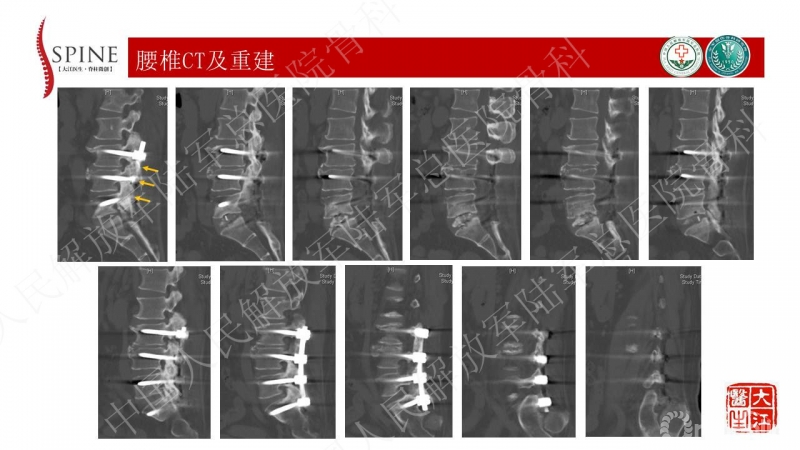

患者主诉为腰痛伴下肢疼痛,腰痛为主,翻身活动、下地时疼痛加重。体格检查也为下腰段的叩压痛,影像可见腰5-骶1断棒。断棒的原因都是力学应力相关的原因,而患者SVA(矢状位垂直轴)不大,全身平衡状态尚可。结合CT表现,应怀疑腰5-骶1节段未融合。

本病例的焦点在患者腰痛的原因,患者明确其腰痛非慢性腰痛,伤后出现。结合病史、体格检查、断棒的表现,主要考虑下腰段的原因。要考虑两个原因,一是腰5-骶1的未融合,断棒后不稳,局部应力集中。二是断棒后局部异常活动,带动瘢痕牵拉硬膜囊及神经根的向背侧牵拉,这种异常活动在残留小关节的抵挡下会引起严重卡压,而出现下肢的疼痛、甚至神经功能损害等。患者行原术区内固定取出,腰5-骶1内固定术,术后取得良好效果,证实患者本次疼痛病因为腰5-骶1节段断棒后应力集中、异常活动。

患者疼痛为伤后出现,不是根性痛表现,而是机械性疼痛,活动及下地时明确。上位节段已融合,考虑到长节段固定后腰5-骶1节段由于杠杆原理出现内固定失败的风险大,术中取出原内固定后,仅行腰5-骶1短节段固定,取得了良好的临床效果。美中不足的是,因椎管内瘢痕粘连重,未重新加强融合,之后需严密随访。